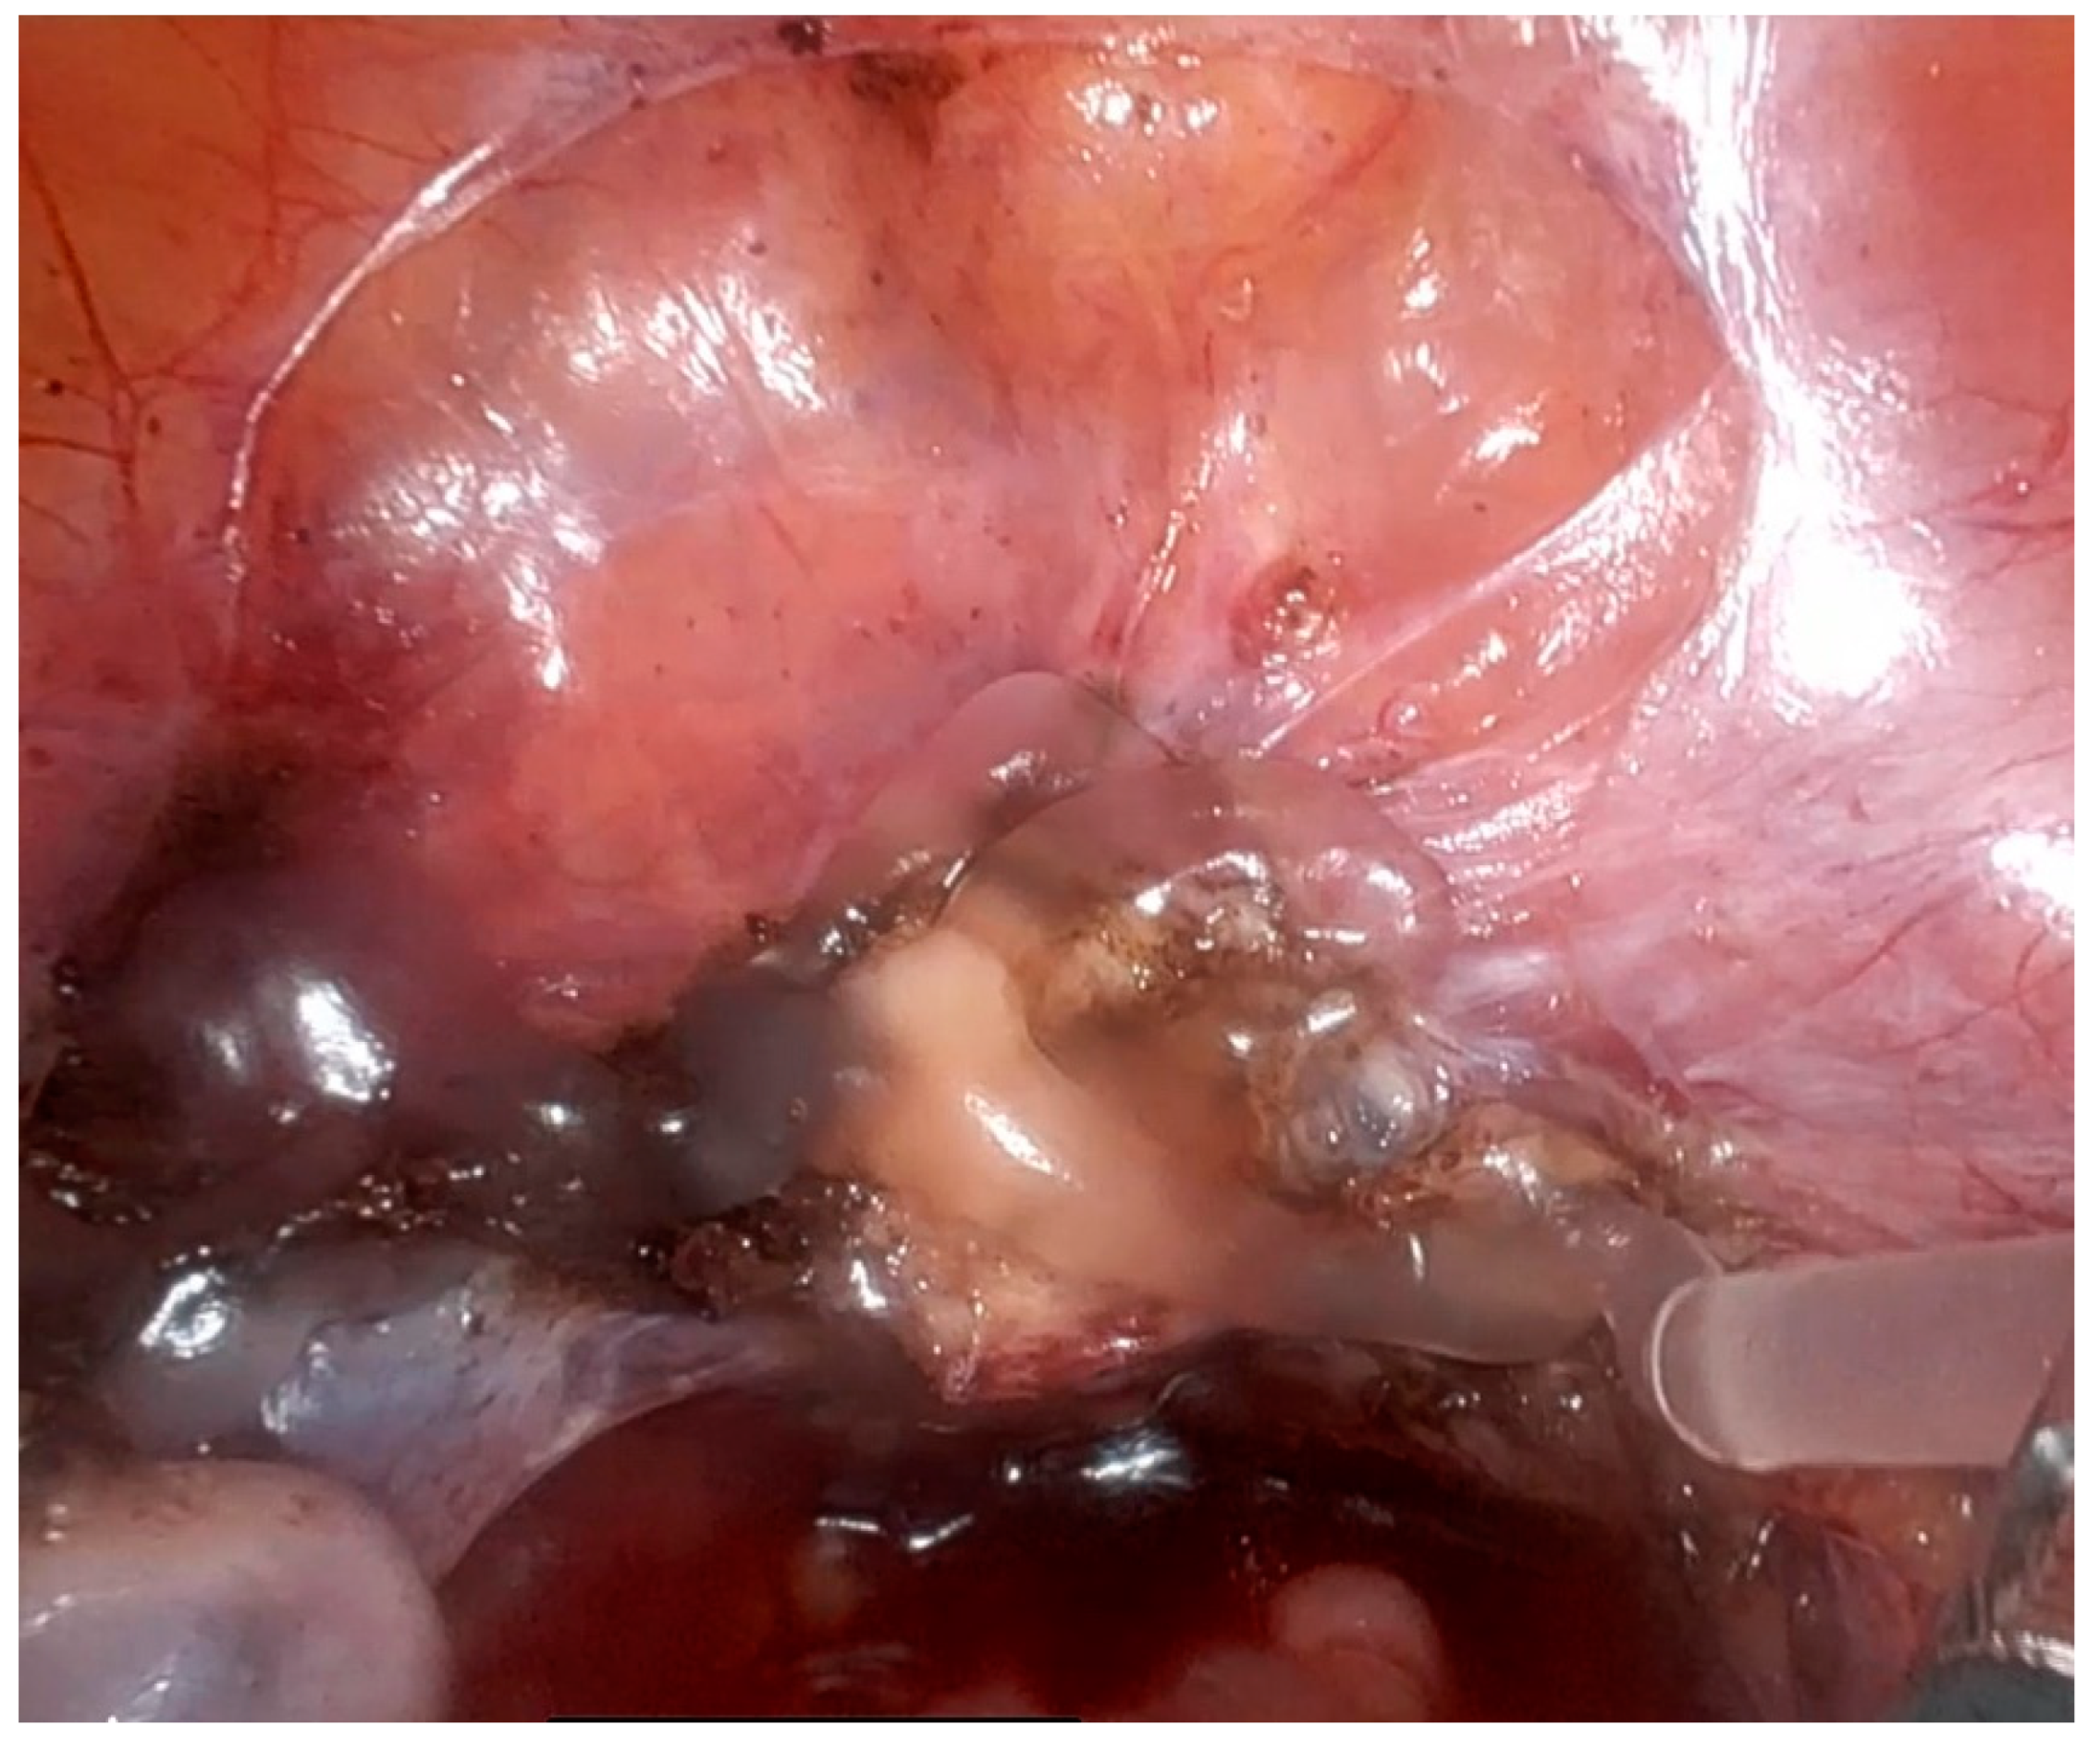

3.1. Adhesion Prevention After Endometriosis Surgery

3.2. Preventing Adhesion Re-Formation After Adhesiolysis Surgery and Neuropelveology

3.3. Ovarian Cysts: Hemostasis and Adhesion Prevention

3.4. Ovarian Carcinoma: Hemostasis and Adhesion Prevention